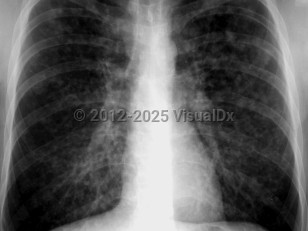

Chest pain, Dyspnea, 50-59 year old Female

Pneumothorax

Spontaneous pneumothoraxSpontaneous pneumothorax